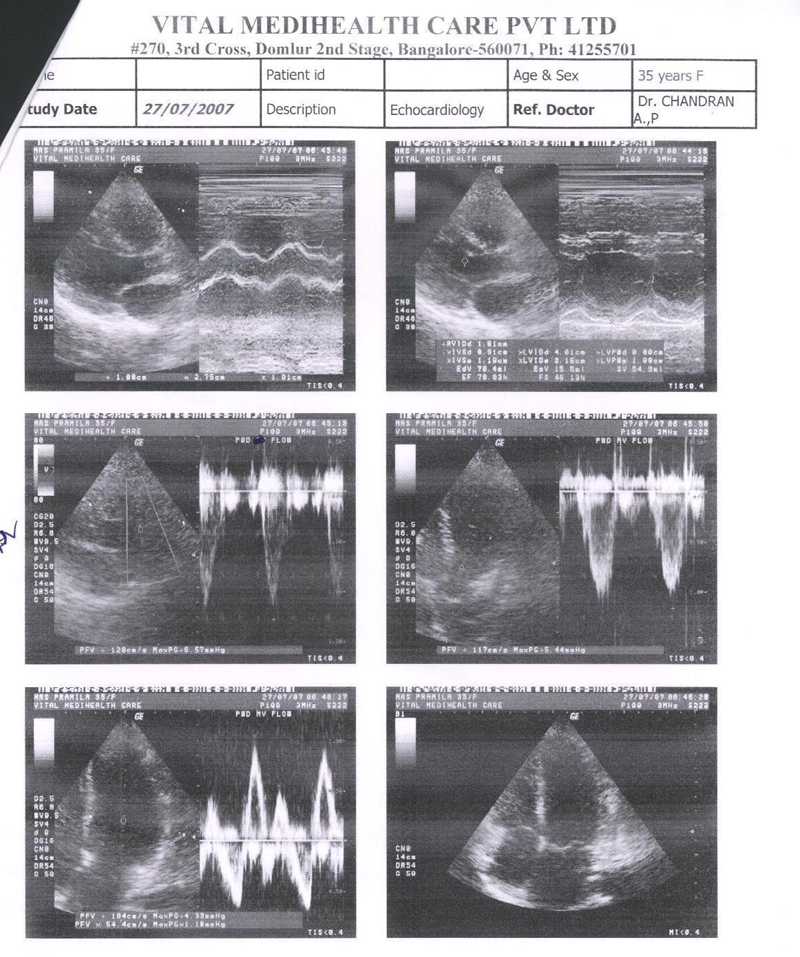

The Echocardiography done on 2nd Nov. 2006 done on Manipal Hospital clearly states Bicuspid and Thickened Aortic Valve, Mild Aortic Stenosis, Concentric LV Hyper trophy. But patient condition from 2nd Nov. to 2nd DEC had already deteriorated and she was supposed to be admitted in the Hospital By 15 th DEC. 2006

The Echocardiography report of 2nd Nov. 2006 is shown in fig 1

FIG 1:- Echocardiography report of 2nd Nov. 2006